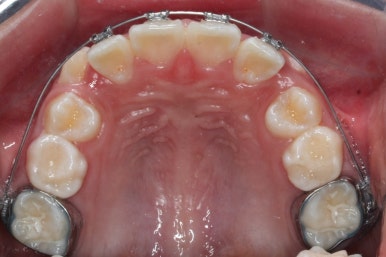

첫 장치 부착한 모습입니다.

아직 유치가 몇 개 남아있기에 장치가 전체적으로 부착되지 않습니다. 우선 앞니 4개만 먼저 치열을 맞추고 위쪽 어금니는 후방 이동을 해주면서 교합을 맞추며 덧니가 내려올 공간을 확보합니다.

연산동덧니교정 키다리아저씨치과에서는 메탈 장치를 사용했습니다.

많이 사용 되는 클리피씨 장치 등의 세라믹 보다는 아이가 양치하기 쉬운 부피가 작고 비용도 덤으로 낮은 메탈장치를 사용했습니다.